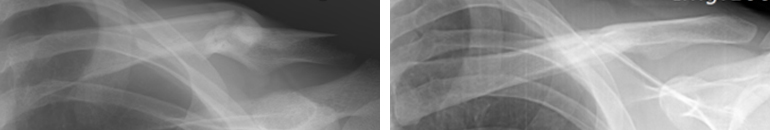

대부분 유합이 잘 되고 기능상 문제없이 잘 낫습니다. 비수술적 방법으로 8자형 붕대를 4~6주간 유지하는 정도의 방법을 선택할 수 있습니다.

8자 붕대를 착용한 모습입니다. 8자 붕대를 착용한 모습입니다.

비수술적 치료로 뼈가 잘 붙은 사진 비수술적 치료로 뼈가 잘 붙은 사진